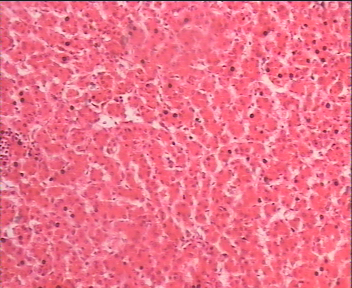

A case of neonatal hemochromatosis is reported in a premature 35-week infant who presented at birth with coffee ground vomiting and gradual appearance of grayish icter and colorless stool. Neonatal hemochromatosis was confirmed by elevated ferritin levels and extrahepatic siderosis detected in liver biopsy.